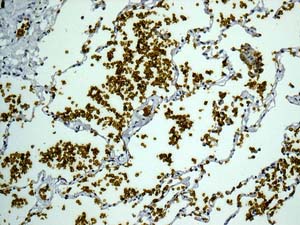

Immunohistochemistry (Formalin/PFA-fixed paraffin-embedded sections) - Alexa Fluor® 647 Anti-Band 3/AE 1 antibody [EPR1426] (AB225080)

IHC image of Band 3/AE 1 staining in a section of formalin-fixed paraffin-embedded normal human placenta*.

The section was pre-treated using heat mediated antigen retrieval with sodium citrate buffer (pH6) in a Biocare Medical NxGen pressure cooker using retrieval settings of 110oC for 20 minutes. Non-specific protein-protein interactions were then blocked in TBS containing 0.025% (v/v) Triton X-100, 0.3M (w/v) glycine and 1% (w/v) BSA for 1h at room temperature. The section was then incubated overnight at +4°C in TBS containing 0.025% (v/v) Triton X-100 and 1% (w/v) BSA with ab225080 at 1/100 dilution (shown in red). Nuclear DNA was labelled with DAPI (shown in blue). The section was then mounted using Fluoromount®.

Image was taken with a confocal microscope (Leica-Microsystems, TCS SP8).